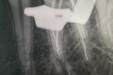

市口腔医院牙体牙髓病2科完成下颌第一磨牙远中颊根双根管治疗--精准攻克复杂根管难题!

2025-10-24|牙体牙髓2科 -